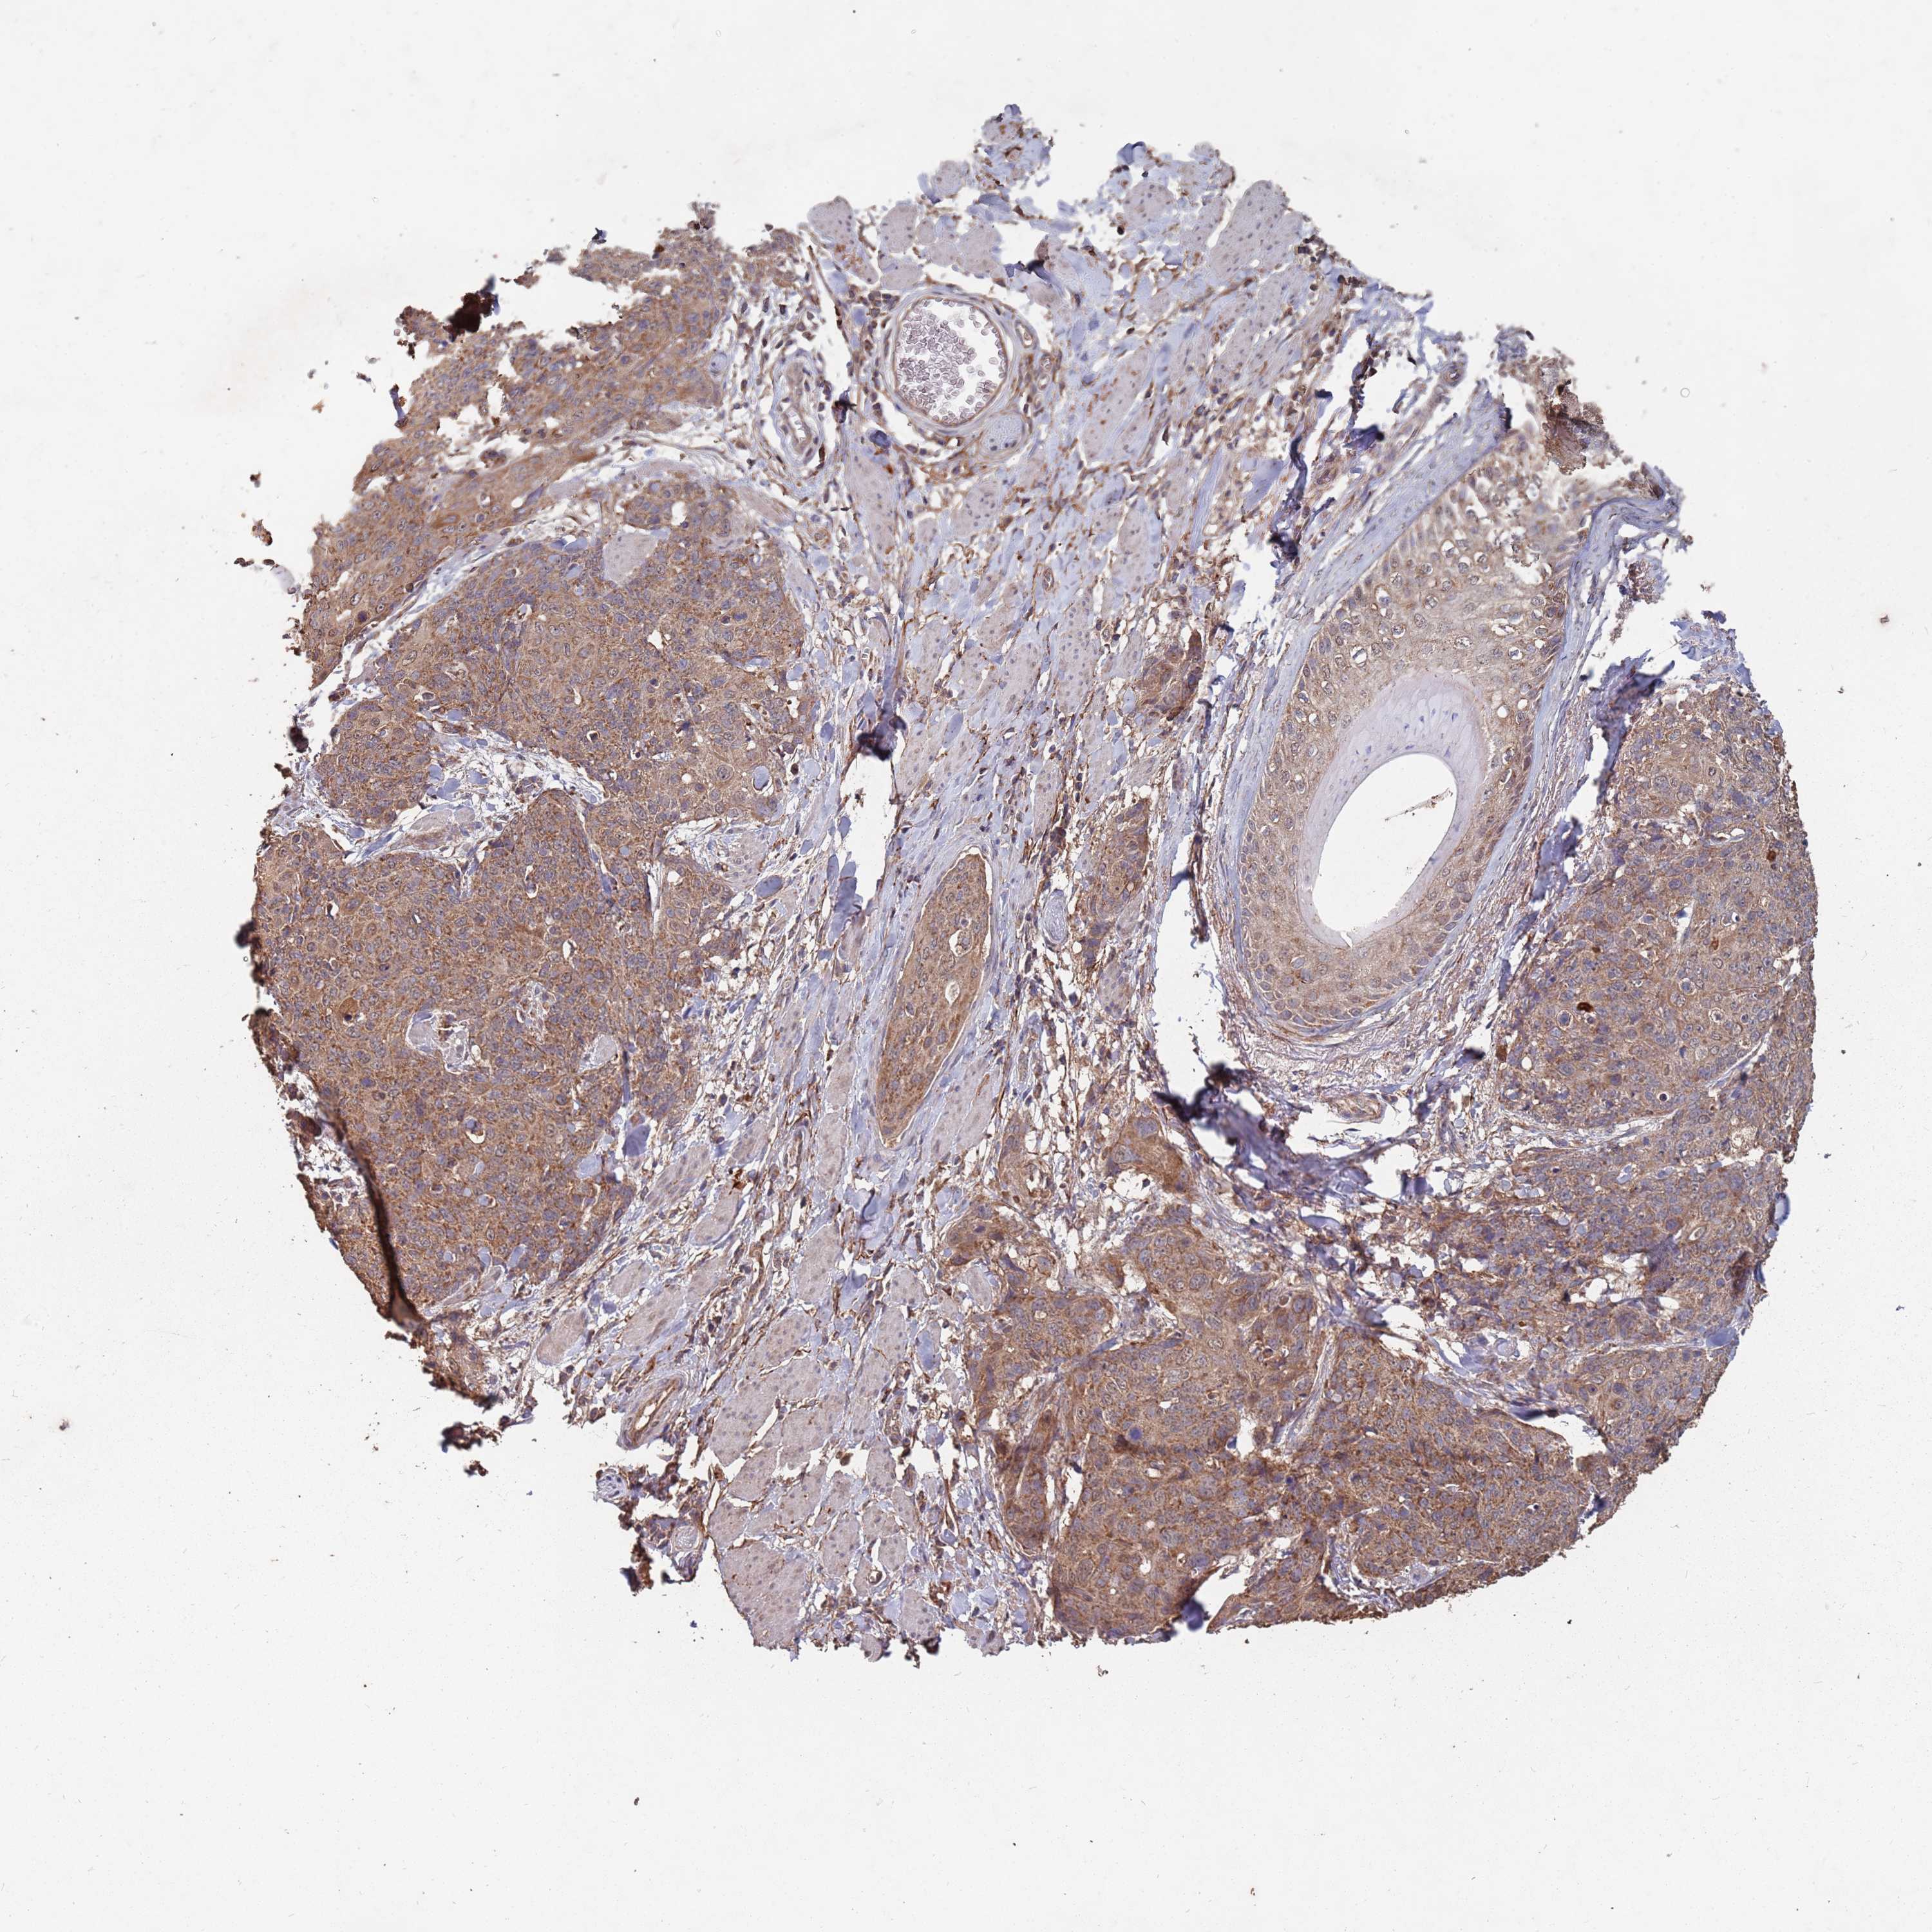

SKIN CANCER - Protein expressioni

A mouse-over function shows sample information and annotation data. Click on an image to view it in a full screen mode. Samples can be filtered based on level of antibody staining by selecting one or several of the following categories: high, medium, low and not detected. The assay and annotation is described here.

Antibody stainingi

Antibody staining in the annotated cell types in the current human tissue is reported as not detected, low, medium, or high, based on conventional immunohistochemistry profiling in selected tissues. This score is based on the combination of the staining intensity and fraction of stained cells.

Each image is clickable and will lead to virtual microscopy that enables deeper exploration of all samples and also displays staining intensity scores, fraction scores and subcellular localization as well as patient and tissue information for each sample.

Antibody HPA020459

Staining

High

Medium

Low

Not detected

Intensity

Strong

Moderate

Weak

Negative

Quantity

>75%

75%-25%

<25%

None

Location

Nuclear

Cytoplasmic/membranous

Cytoplasmic/membranous,nuclear

Basal cell carcinoma

Squamous cell carcinoma, NOS

Squamous cell carcinoma, metastatic, NOS